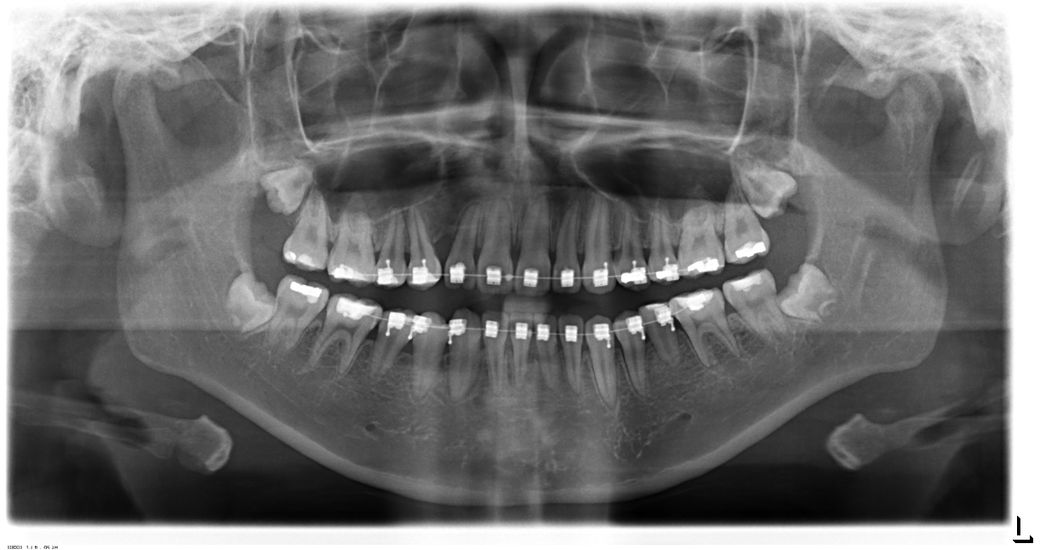

2번째 사진은 첫번째 치아교정 중단하고 찍은 엑스레이입니다. 이때도 턱 왼쪽으로 좀 휘어졌고 왼쪽 턱관절 통증+ 오른쪽 턱관절 뭔가 빠진느낌+ 안면비대칭이 더 심해보이고 입술도 왼쪽 올라가고 오른쪽 내려감.

• 2번 째 사진